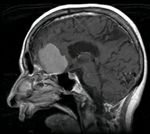

Опухолью мозга называют группу новообразований, различных по месту локализации и характеру возникновения. Опухоли мозга, как и любые другие, подразделяются на злокачественные, которые называют раком, и доброкачественные.